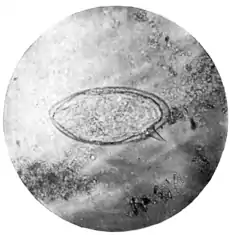

(Microphotograph: Dr. Bell.) ||Fig. 2.—Lateral-spined egg of Schistosomum mansoni.

(Microphotograph: Dr. Kerr.)